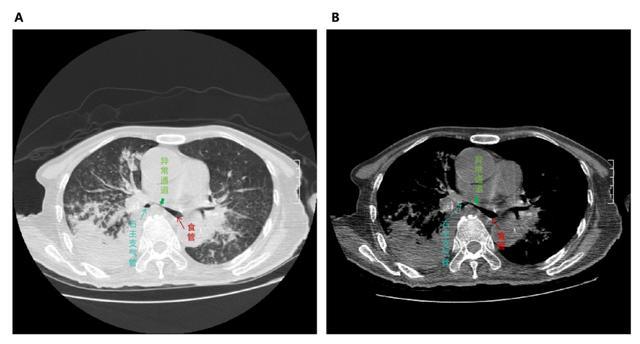

原本该走进消化道这个“热带雨林”被消化掉的紫米粥,似乎迷了路,穿越到本来与消化道不相往来的呼吸道,这到底发生了什么?为了明确病因,患者完善了肺部CT,发现食管与支气管之间开放了异常通道——出现了支气管食管瘘,并且继发了严重的肺部感染。

(▲患者肺部高分辨CT提示食管与右主支气管连通,形成支气管食管瘘。)